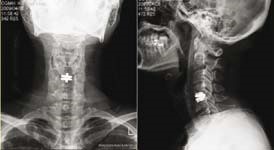

55歳的陸先生是位工程師,在2016年11月來求診,兩年來他手部 麻木 痺痛,尤其是右手拇指及二指,後來更出現 手部乏力 、走路時 腳軟 無力的情況。兩年來看了不同科的西醫及中醫,亦接受了 物理治療 及 脊醫 的保守治療。臨床的神經反射檢查顯示陸先生有頸椎中樞神經嚴重受壓的可能,隨後的 磁力共振 醫學造影確診了頸椎第四、五及第五、六節出現嚴重退化及 椎間盤突出 ,而且嚴重壓向脊髓中樞神經,脊髓神經有變形、扁平及 水腫 現象。

陸先生最後聽從醫生的醫學意見,入院進行了四小時的神經外科微創手術 ─ 頸椎前路椎間盤切除及椎體融合術,手術目的是為脊髓中樞神經減壓及鞏固頸椎的穩定性。手術後陸先生臥床休息一晚,第二天早上他發現四肢已經沒有麻木痺痛的感覺,四肢肌肉力度亦有明顯改善。在醫生的監察下他下床走動,發覺雙腳站立地面上時的感覺比手術前實在而且穩健得多,走起路來雙腳力度及步履明顯進步同時相當平穩。從 X-光 及 磁力共振 觀察,頸椎第四、五及第五、六節脊髓受壓程度已大大改善。陸先生當天下午,即手術後24小時便出院回家了。